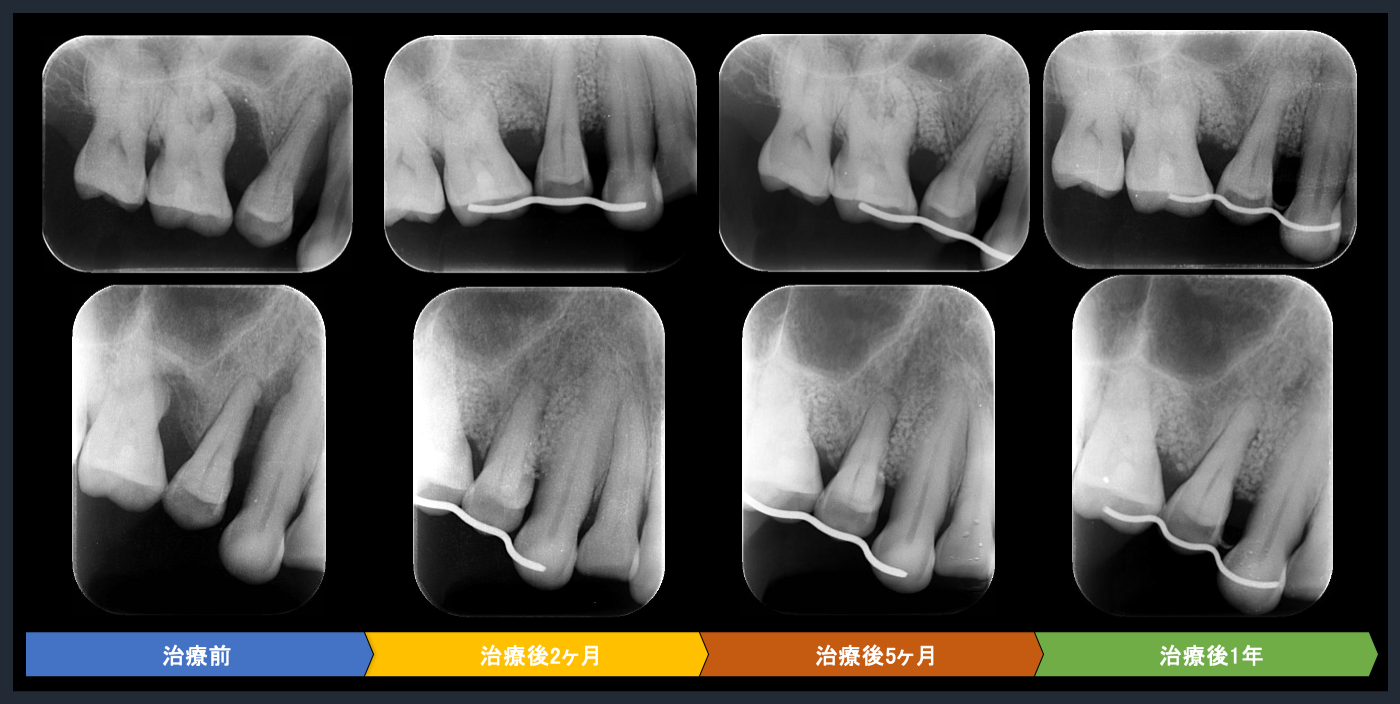

| 概要 | 歯周病が進行しており、右上臼歯部に重度の骨吸収像が認められます。失われた骨を再生し、歯の生存率を高めることを目的に、再生療法を試みました。良好な結果を得ることができました。問題なく使っていただいております。 再生療法を行う利点としては、ポケットが浅くなるので、患者様ご自身でのブラッシングで管理し、コントロールすることが可能になります。もちろん定期的なメインテナンスは必要不可欠です。 |

歯周基本治療後の再評価

Post-treatment evaluation

Post-treatment evaluation

歯周基本治療後の再評価

Post-treatment evaluation

Post-treatment evaluation

歯周組織再生療法の評価

Post-treatment evaluation

Post-treatment evaluation

歯周組織再生療法の評価

Post-treatment evaluation

Post-treatment evaluation

歯周組織再生療法の評価

Post-treatment evaluation

Post-treatment evaluation

歯周組織再生療法の評価

Post-treatment evaluation

Post-treatment evaluation

歯周組織再生療法の評価

Post-treatment evaluation

Post-treatment evaluation

歯周組織再生療法の評価

Post-treatment evaluation

Post-treatment evaluation

歯周組織再生療法の評価

Post-treatment evaluation

Post-treatment evaluation